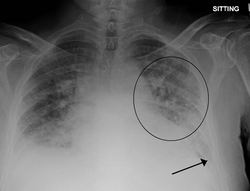

Ağ ciyərin ödemi – arterial kapillyarlardan süzülən mayenin miqdarı venoz kapillyarlarla və limfa sistemi ilə çəkilən mayedən artıq olduqda baş verən xəstəlik. Ağ ciyərin ödemi qan dövranının sol mədəcik tipli pozulması, böyrəklərin bəzi zədələnmələri və s. səbəblərdən inkişaf edir.